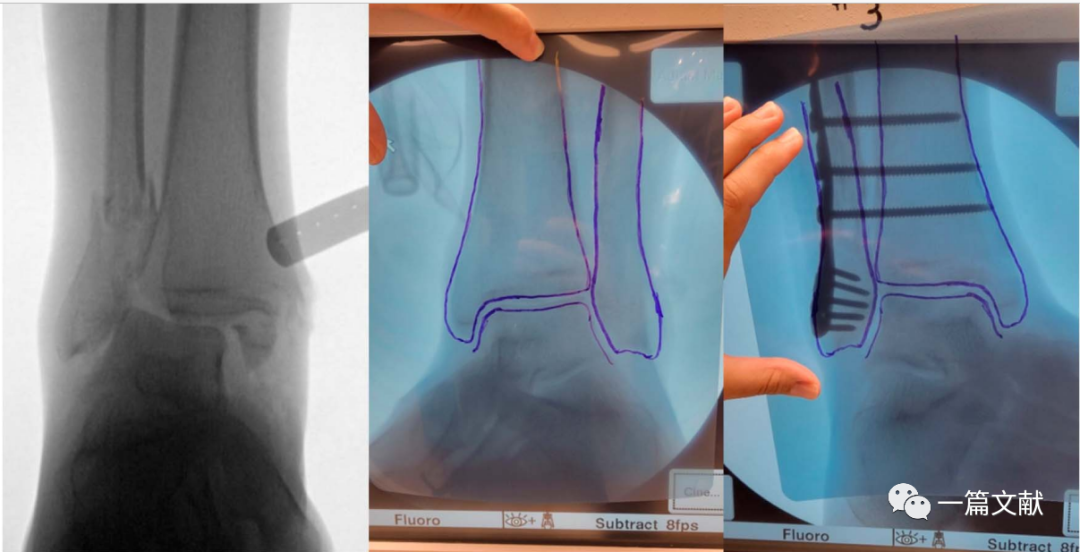

2、腕关节手术

虽然一般认为,术中恢复桡骨远端23°尺偏角,11°掌倾角,13mm的桡骨高度,即获得了良好的骨折复位。但是存在个体差异,例如尺骨变异患者。故此时,将患者健侧肢体作为参考对象最可靠。如下图:

左侧为健侧临摹图,右侧为骨折图

将此临摹图翻转后作为基准,进行骨折复位与固定